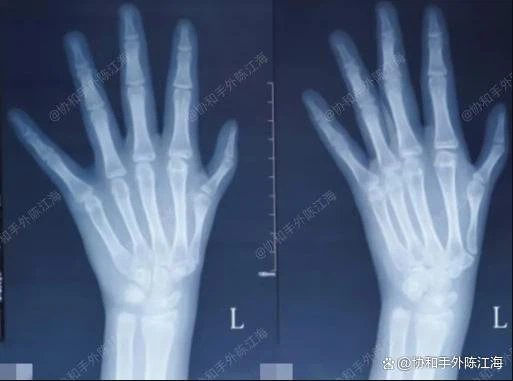

Namun,hipoplasia ibu jari tipe IIterkadang lebih sulit dideteksi dan mungkin diabaikan oleh orang tua. Hal ini karena hipoplasia ibu jari tipe II seringkali tidak memiliki perbedaan yang mencolokpenampilandari ibu jari normal. Namun, begitu Anda memahami karakteristiknya, mudah untuk mendiagnosisnya, dan pembedahannya pun mudah dan tepat sasaran.

Meskipun hipoplasia ibu jari tipe II mungkin tampak "baik-baik saja", otot tenar belum berkembang dengan baik, sehingga area ini terasa kurang penuh saat disentuh. Ibu jari mungkin tampak lebih tipis, dan sudut di mana anak dapat membuka celah ibu jari-telunjuk terbatas.

Jika ruang selaput pertama anak kecil, mereka tidak akan dapat menggenggam benda dengan bebas, dan lebih mengandalkan jari-jari mereka untuk menjepit. Orang tua dapat mengamati dengan saksama postur menggenggam anak mereka saat bermain dengan mainan dan menguji sudut bukaan ibu jari.

Anak-anak dengan hipoplasia ibu jari tipe II biasanya memiliki stabilitas yang buruk pada sendi metakarpofalangeal. Jika orang tua menyentuh jari-jari anak, mereka mungkin merasakan kelonggaran yang nyata. Hal ini dapat menyebabkan anak mengalami kesulitan memegang pena atau membawa air dengan stabil.